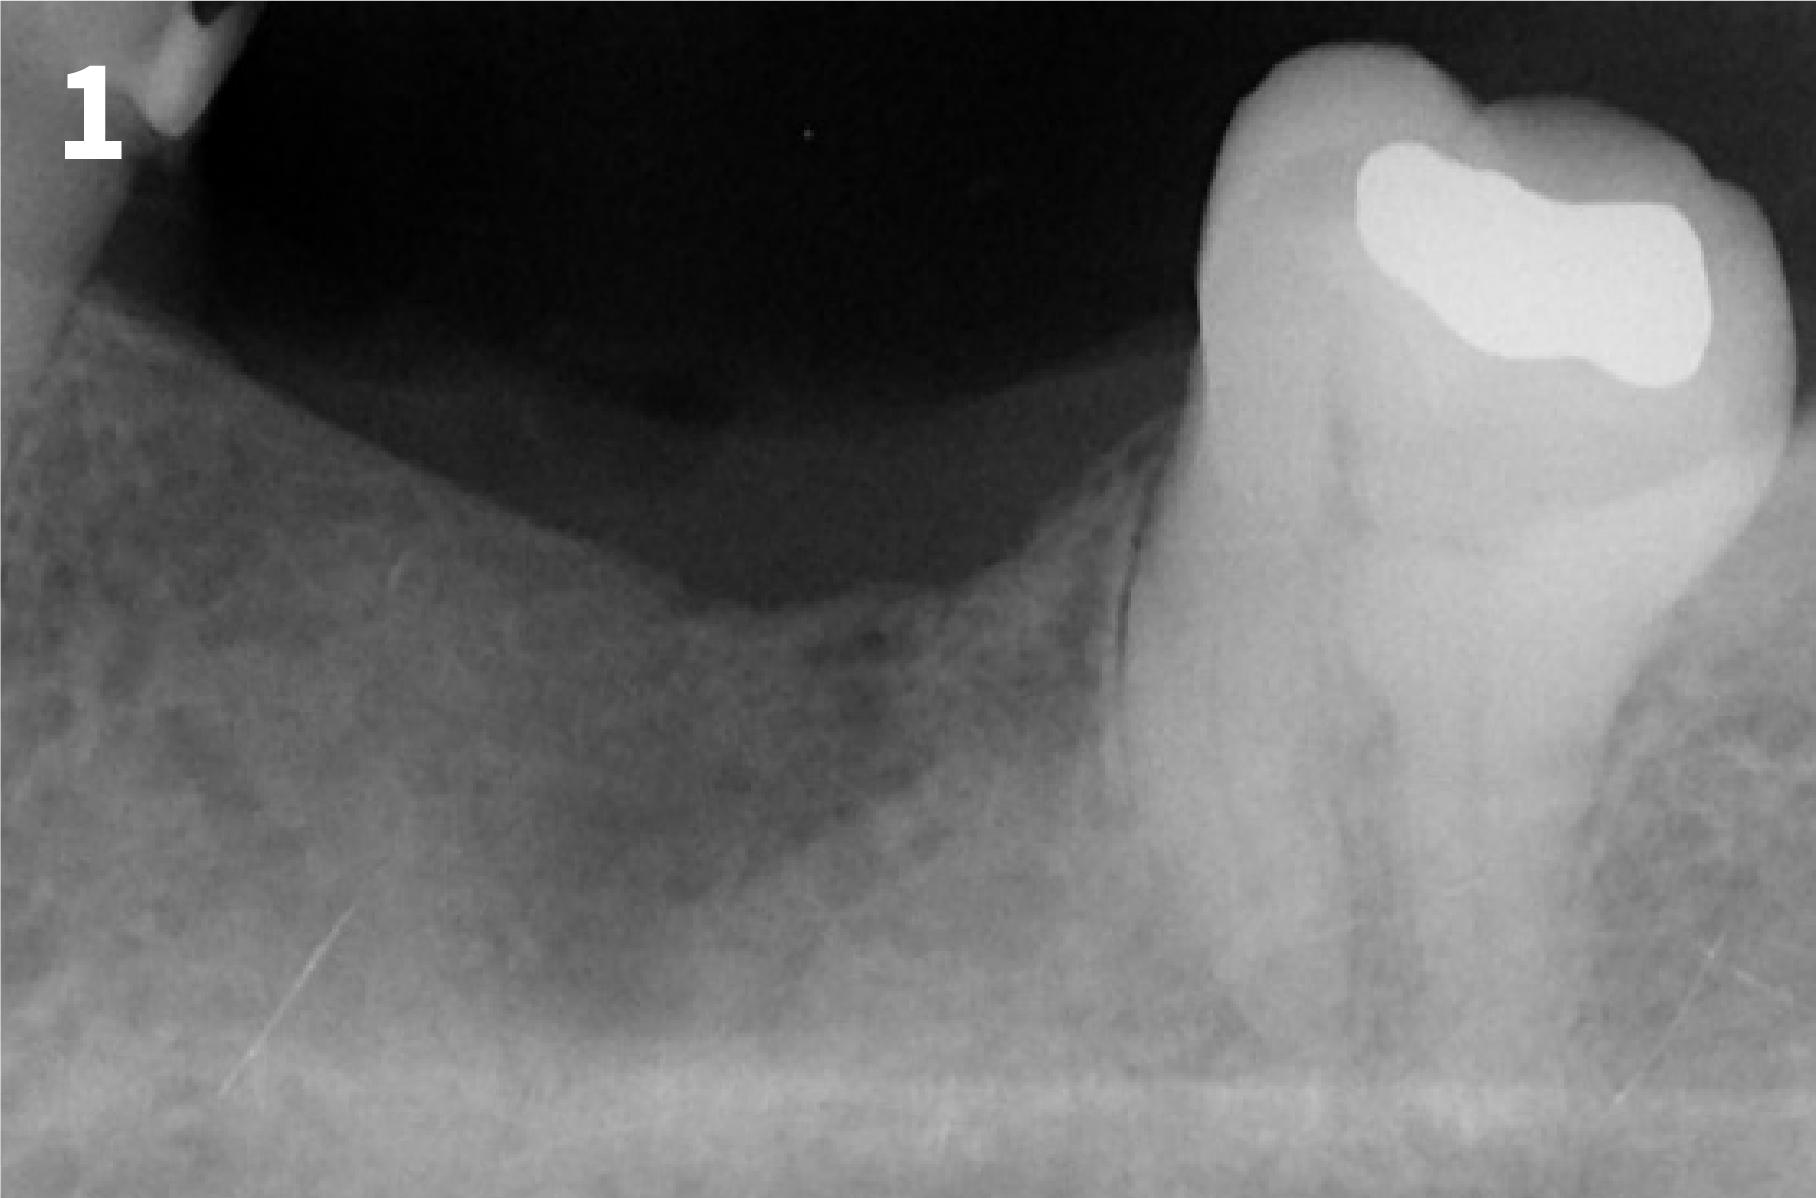

Case 2: Minor Bone Augmentation